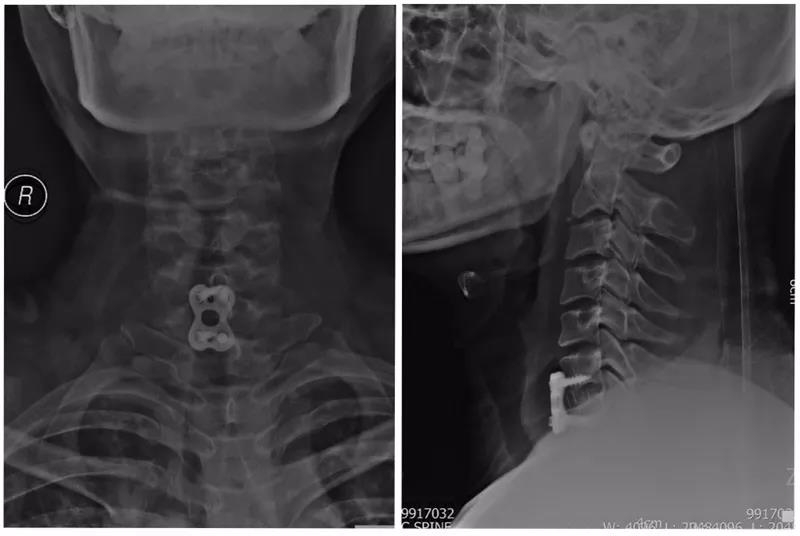

术后X线正侧位片